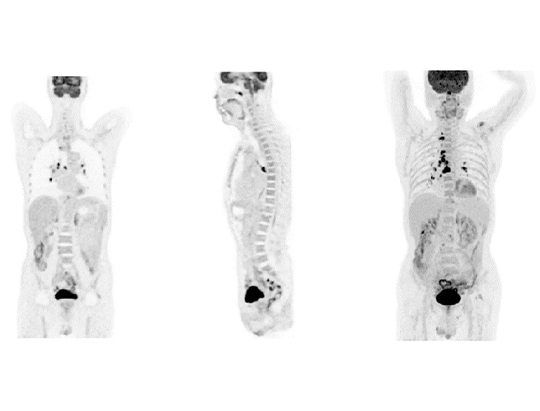

The uMI 550 makes digital PET/CT accessible to all. Built with uEXPLORER® PET technology inside, the uMI 550 enables academic level image quality in oncology, cardiology, and neurology scanning. Born with AI this system utilizes AI-empowered workflow and image reconstruction based on total-body data. This air-cooled system is designed to fit in your room with minimal infrastructure investment and is available for mobile units.

The uMI 550, born with AI, enables high-speed scanning without sacrificing image quality by combining the advanced AI iterative reconstruction engine trained with uEXPLORER® total-body PET data and a predictive AI-empowered workflow.